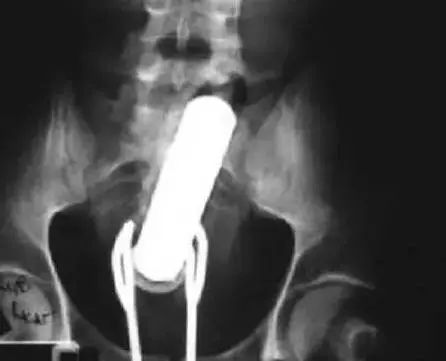

3、下图不多解释了!振动棒深陷“菊花”弄不出来,然后患者试图用沙拉钳来抓振动棒,结果因为沙拉钳太大被卡住了……